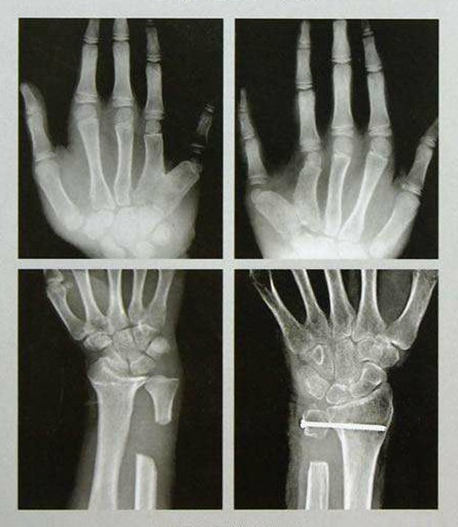

手足外科設(shè)有床位40張,舟山市醫(yī)學(xué)會(huì)手足外科專(zhuān)業(yè)委員會(huì)主任委員姜德欣主任醫(yī)師擔(dān)任學(xué)科帶頭人。科室提供上下肢和手足部的各種骨折、外傷、感染、畸形、功能障礙的手術(shù)治療,復(fù)雜創(chuàng)傷性四肢的保肢、斷指(趾)再植手術(shù),及各種軟組織缺損的修復(fù)、周?chē)窠?jīng)損傷、血管損傷的治療及糖尿病足等的綜合治療。